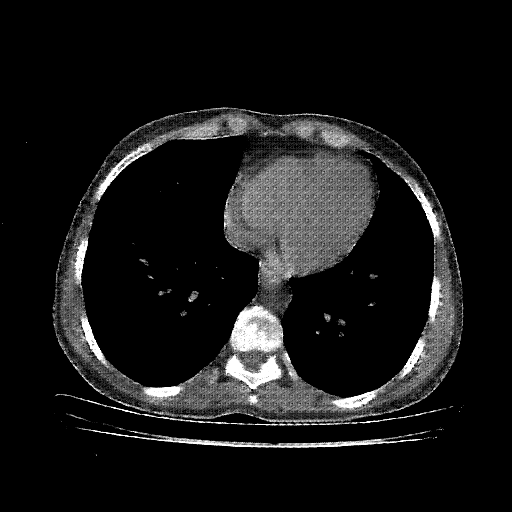

Image Grid

4×3 grid: Rows show different image types (Original NATIVE, Reconstructed NATIVE, Original VENOUS, Generated VENOUS), Columns show windowing techniques (No Window, Lung Window, Mediastinum Window)

Reconstructed NATIVE CT scan (cycle consistency)

No window - Raw intensity values

Reconstructed NATIVE CT scan (cycle consistency)

Lung window (WL -600, WW 1500 → Low −1350, High +150)

Reconstructed NATIVE CT scan (cycle consistency)

Mediastinum window (WL 40, WW 400 → Low −160, High +240)

Windowing Parameters

- No Window: Raw intensity values without windowing

- Lung Window: WL -600, WW 1500 → Low −1350, High +150 (optimal for pulmonary structures)

- Mediastinum Window: WL 40, WW 400 → Low −160, High +240 (optimal for soft tissues)